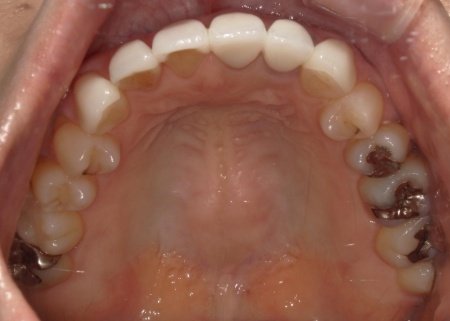

60代女性 古い被せ物を作り直して審美性を改善させた症例

「20年前、受け口を改善するために審美歯科で被せ物による治療を受けたが、仕上がりに不満が残った。最近、再び気になるようになったため、再治療が可能かを相談したい」とご相談いただきました。

拝見したところ、上下前歯には金属製の土台「メタルコア」を使用した被せ物(クラウン)が装着されており、被せ物と歯茎の境目付近が黒くなっていました。

また、保険適用の白い詰め物(コンポジットレジン)が充填されている部分には変色が見られます。ご自身の歯、被せ物、コンポジットレジン、それぞれの色調が異なっていることで審美性に影響が出ているため、上下前歯(合計12本)の被せ物と詰め物を新しくする必要があると診断しました。